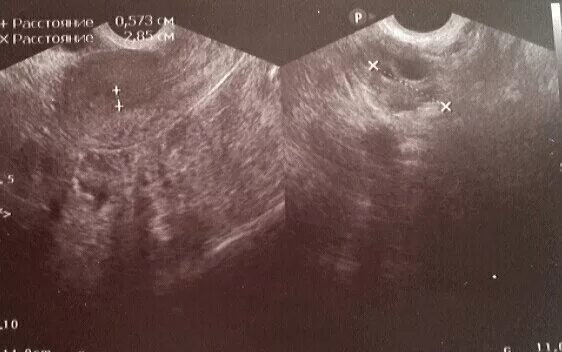

Почему увеличена матка после